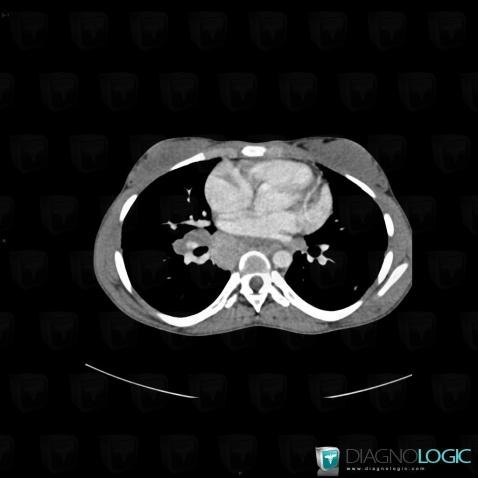

Sarcoïdose, Médiastin, Scanner

Voici les informations spécifiques à l'image clé ci dessus:

- Diagnostic Sarcoïdose, Localisation(s) Médiastin, comportant les gammes Masse médiastinale supérieure